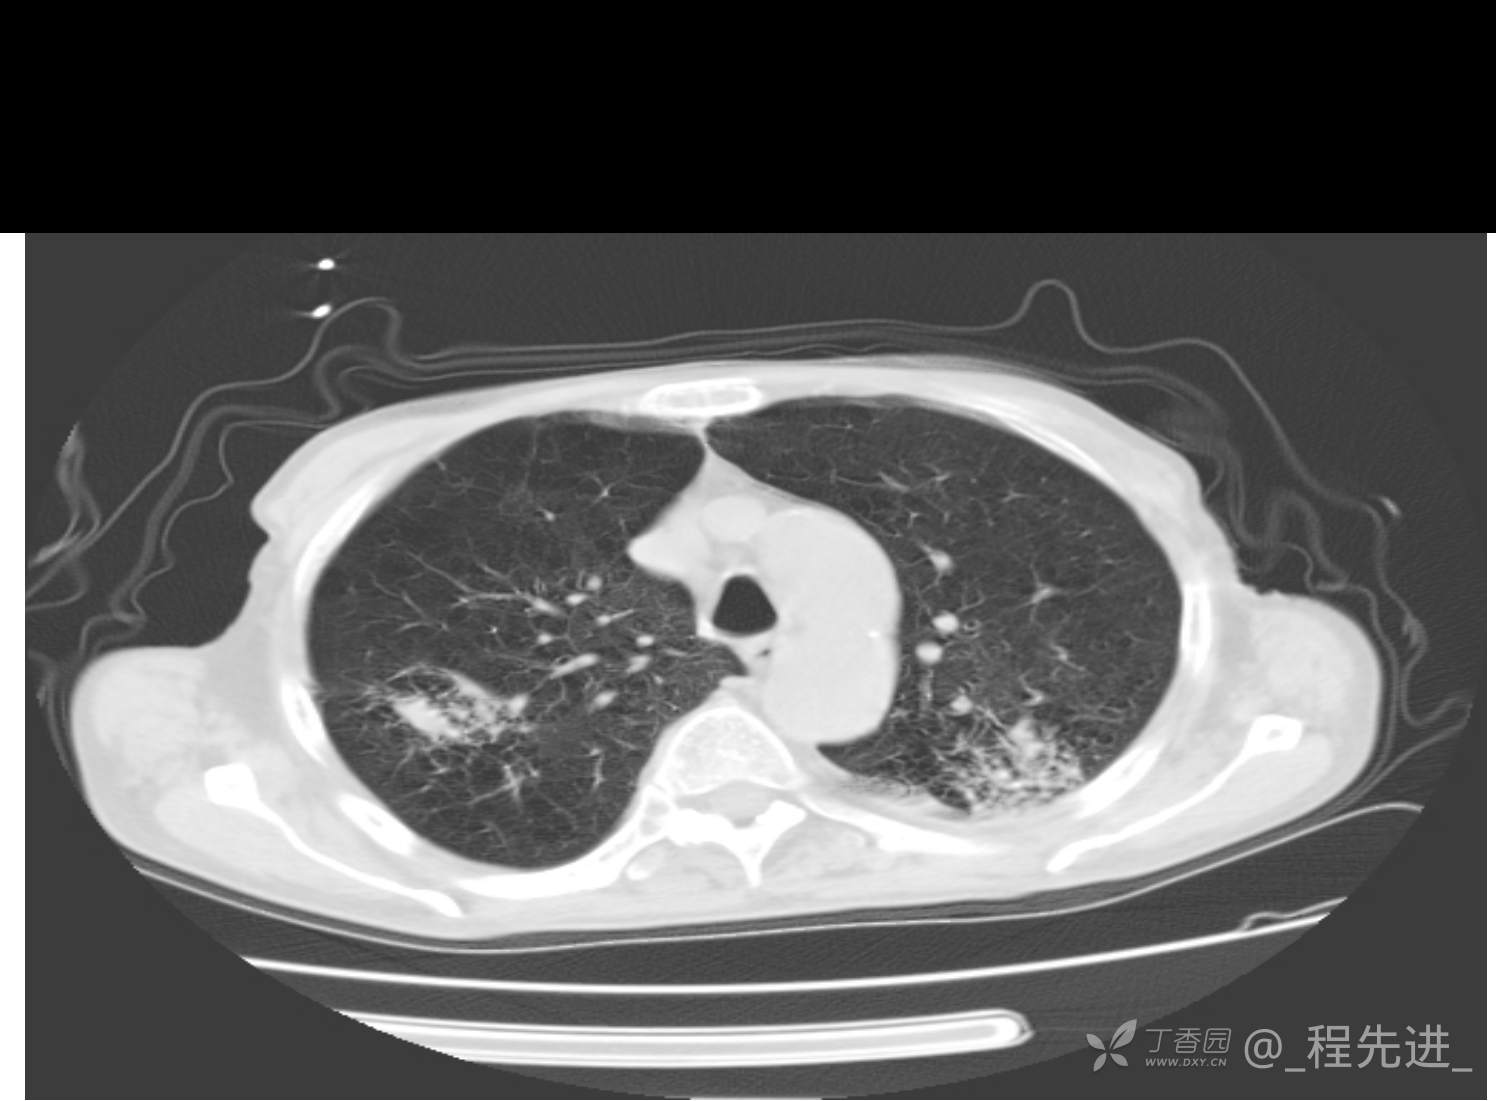

患者性别:男

患者年龄:81岁

简要病史:反复咳嗽、咳痰20余年,加重1周。两肺呼吸音低,可闻及散在干湿啰音。